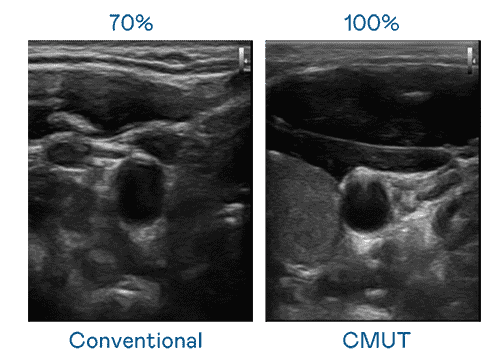

CMUT 技术是一种用电容式微机电元件来产生超音波讯号的技术。。与传统 PZT 压电式技术相比,,,,CMUT 频宽增加 30%,,,,更宽频的超音波讯号让影像解析度大幅提升,,,是实现高影像品质医疗超音波扫描、、、促进精准医疗发展的关键技术。。。

超音波影像的解析度高低,,,,首先取决于探头能发出的讯号频宽。。。z6mg·人生就是博 CMUT 可提供高清晰的超音波讯号,,提供高频宽、、、高灵敏度、、、影像纹理细节更高的超音波影像,,,,协助医护人员缩短影像判读时间及利用精准的医疗影像进行诊断。。